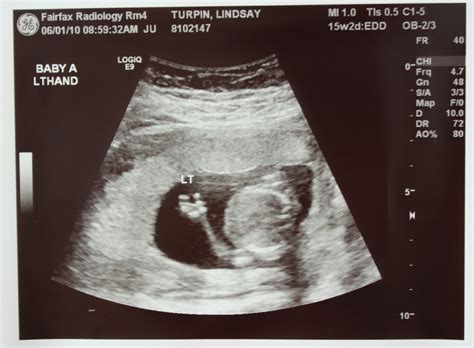

Understanding the Ultrasound Images

The 16 week ultrasound provides detailed images of the baby’s anatomy. Healthcare providers will look for specific features to ensure everything is developing normally. Some of the key areas of focus include:

• Limbs: The length and structure of the arms and legs, including the hands and feet.